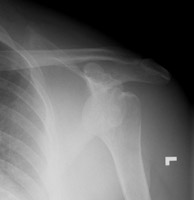

- Click on the image for a larger versionBAxillary radiograph of the left shoulder. This demonstrates the anterior dislocation as well as better depicts the coracoid fracture.